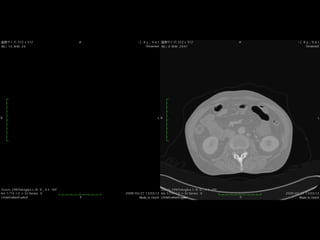

Pain Point:

Imaging 3D structure

from 2D image sequence

DICOM Viewerを使ってみる。

Windows Level, Windows With, Dicom Tagについて理解をす

る。

ダイナミックCT